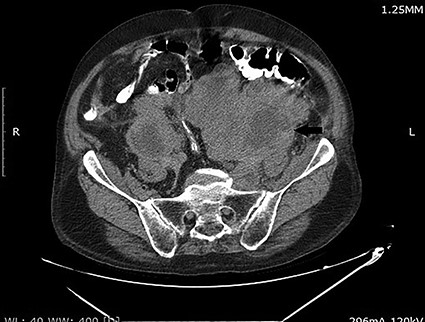

Computed tomography (CT) scan of abdomen and pelvis with Per os contrast showed a partially necrotic and lobulated retroperitoneal mass extending along para-caval and para-aortic regions on both sides till the pelvis and enlarged prostate gland measured 60 g (Fig. 1). The left kidney shows severe hydronephrosis.

CT scan of the abdomen and pelvis demonstrating a large retroperitoneal mass (arrow).